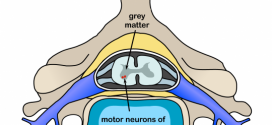

La parálisis de aran-duchenne. Atrofia muscular progresiva mielógena con afección de las raíces nerviosas octava cervical y primera dorsal, con afectación de las neuronas motoras. Producen parálisis fláccida y atrofias musculares de los flexores de los dedos y el cubital anterior, entre otros. Afecciones del sistema nervioso central, cerebral, etc, de probable patogenia autoinmune, etc, que se caracteriza por placas …